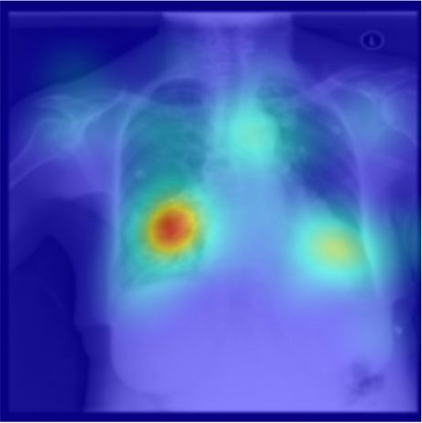

The way humans attend to, process and classify a given image has the potential to vastly benefit the performance of deep learning models. Exploiting where humans are focusing can rectify models when they are deviating from essential features for correct decisions. To validate that human attention contains valuable information for decision-making processes such as fine-grained classification, we compare human attention and model explanations in discovering important features. Towards this goal, we collect human gaze data for the fine-grained classification dataset CUB and build a dataset named CUB-GHA (Gaze-based Human Attention). Furthermore, we propose the Gaze Augmentation Training (GAT) and Knowledge Fusion Network (KFN) to integrate human gaze knowledge into classification models. We implement our proposals in CUB-GHA and the recently released medical dataset CXR-Eye of chest X-ray images, which includes gaze data collected from a radiologist. Our result reveals that integrating human attention knowledge benefits classification effectively, e.g. improving the baseline by 4.38% on CXR. Hence, our work provides not only valuable insights into understanding human attention in fine-grained classification, but also contributes to future research in integrating human gaze with computer vision tasks. CUB-GHA and code are available at https://github.com/yaorong0921/CUB-GHA.